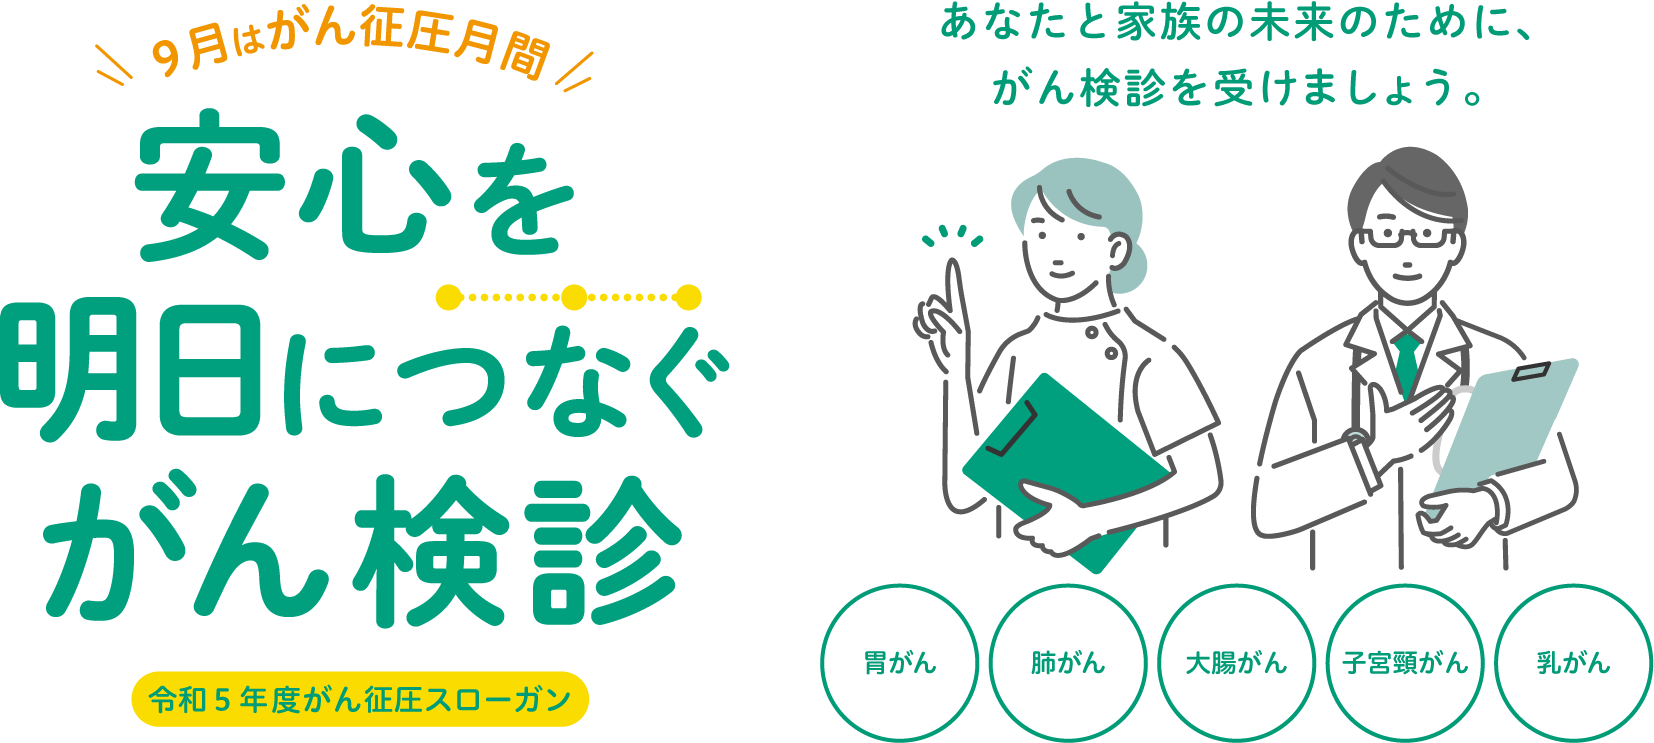

がん征圧⽉間について

毎年9⽉を「がん征圧⽉間」と定め、がんとその予防についての正しい知識の徹底と早期発⾒・早期治療の普及に全国の組織をあげて取り組んでいます。

令和5年度がん征圧スローガンは「安心を明日につなぐがん検診」

富⼭県健康増進センターは、対がん協会グループとして「がん征圧」に向けての啓蒙普及活動や各種がん検診を実施しています。

未来の⾃分のために、胃がん・肺がん・⼤腸がん・子宮頸がん・乳がん検診を受けましょう。